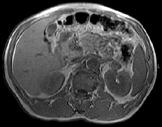

问题 男,52岁,下肢无力伴多饮多尿2 年余,实验室检查:低血钾,血醛固酮水平及24h 尿醛固酮定量超过正常值,MRI检查如图所示,应诊断为 ( )

选项 A、左肾上腺髓脂瘤 B、左肾上腺转移瘤 C、左肾上腺腺瘤 D、左肾上腺嗜铬细胞瘤 E、左肾上腺囊肿

答案 C